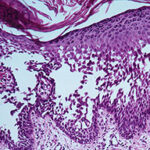

Histopathology. Although, as in Darier’s disease, early lesions may show small suprabasal separations, so-called lacunae, fully developed lesions show large separations, that is, vesicles and even bullae, in a predominantly suprabasal position . Villi, which are elongated papillae lined by a single layer of basal cells, protrude upward into the bulla, and in some cases, |

narrow strands of epidermal cells proliferate downward into the dermis. Many cells of the detached stratum malpighii show loss of their intercellular bridges; thus, acantholysis affects large portions of the epidermis. |

Individual cells and groups of cells usually are seen in large numbers in the bulla cavity. Despite the extensive loss of intercellular bridges, the cells of the detached epidermis in many places show only slight separation from one another, because a few intact intercellular bridges still hold them loosely together. This quite typical feature gives the detached epidermis the appearance of a dilapidated brick wall. |

Many of the cells of the stratum malpighii that have lost all or most of their intercellular bridges show a fairly normal cytoplasm and a normal nucleus in which mitotic activity has even been observed . Some of the acantholytic cells, however, have a homogenized cytoplasm, suggesting premature partial keratinization. In some instances, such acantholytic cells with premature keratinization resemble the grains of Darier’s disease. Occasionally, a few corps ronds are present in the granular layer . |